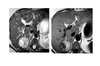

Eosinophilic oesophagitis

Barium - Concentric, ring-like strictures of oesophagus

**Not transient - Permanent **

DDx

feline oesophagus

- folds1-2 mm thick and run horizontally around the entire circumference of the esophageal lumen.

- The findings are transient, seen following reflux and not during swallowing.

- Associated with GORD

- distal two-thirds of the thoracic esophagus